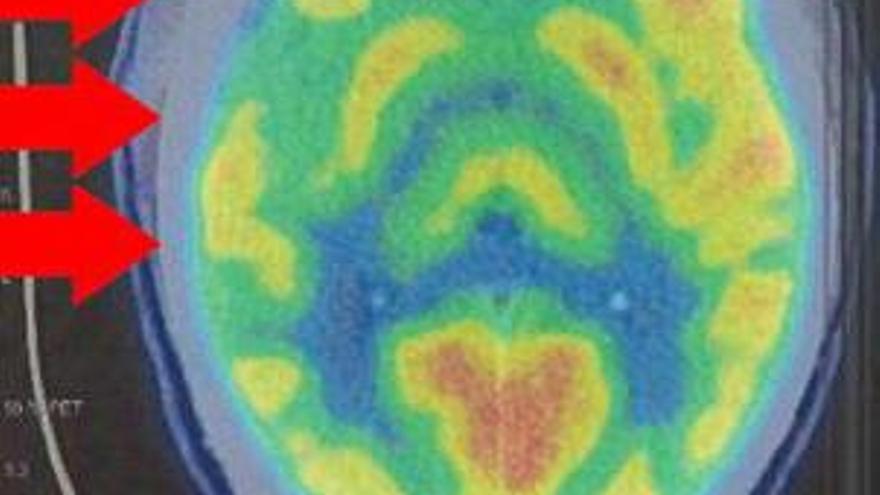

En el cerebro se deciden nuestros actos. También los más atroces. La estructura y el funcionamiento del cerebro de Patrick Nogueira, un joven que tenía 19 años cuando asesinó a sus tíos, Marcos y Janaina, y a sus sobrinos Carolina y David en la casa de Pioz (Guadalajara), eran un enigma hasta que fueron examinados por el doctor Antonio Maldonado, jefe de servicio de Medicina Nuclear del hospital universitario Quirónsalud de Madrid. Tras realizarle un TAC (imágenes construidas por un ordenador a partir de las obtenidas por rayos x) y un PET (inyección de sustancias radiactivas para luego analizar cómo funciona su mente), el especialista concluye que el cerebro de Nogueira «no se ajusta a los criterios de normalidad», según el informe encargado por la defensa del joven.

Los estudios realizados al asesino de Pioz han detectado una «marcada disminución de la actividad neuronal» en varias zonas del lóbulo temporal derecho de su cerebro. Varios autores han vinculado una atrofia de esa zona con el desarrollo de la psicopatía, aunque no hay resultados concluyentes.

El psiquiatra José Miguel Gaona y el psicólogo Jonatan Quejido, contratados por su defensa, n en apreciar un trastorno de personalidad antisocial, pero defienden que esas anomalías en su cerebro constituyen un «daño neurológico que tiene repercusiones» sobre su conducta. Creen que tiene las facultades alteradas y piden que se le realice un estudio «más profundo», sin descartar corregirle en un quirófano esas anomalías.